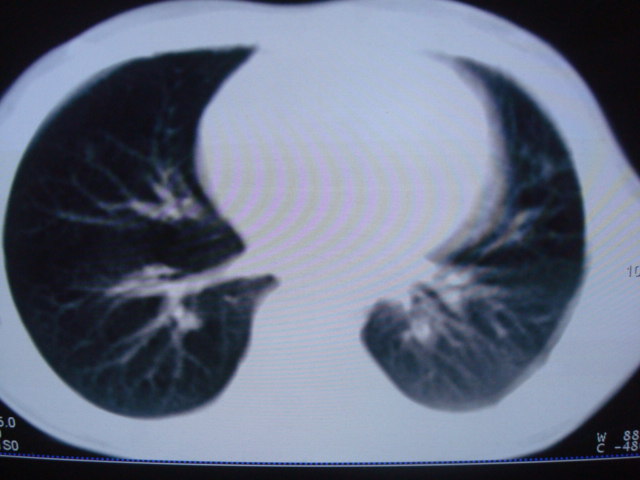

标题: PED0869:男,10岁,肺内多发结节+胸水 [打印本页]

标题: PED0869:男,10岁,肺内多发结节+胸水

男,10岁,左胸痛,发热轻,血象高。后到省级权威医院治疗,病情明显好转,结果几天后公布。老机器,图像质量差,见谅。